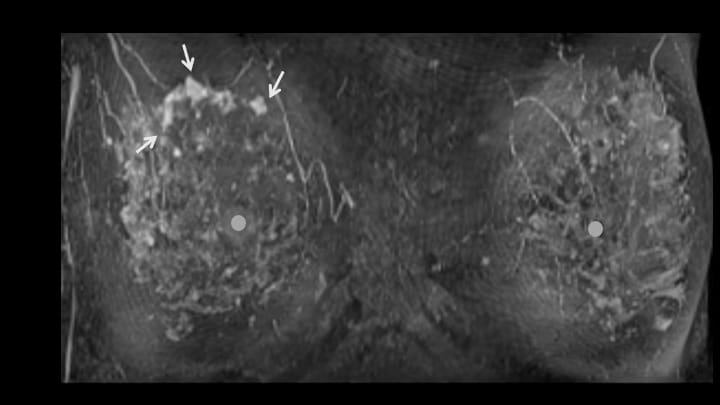

1. ダイナミックMRI 早期相MIP画像(正面)

●は乳頭。造影病変は横に長く、腺葉を超えて広がるように見える(regional)。